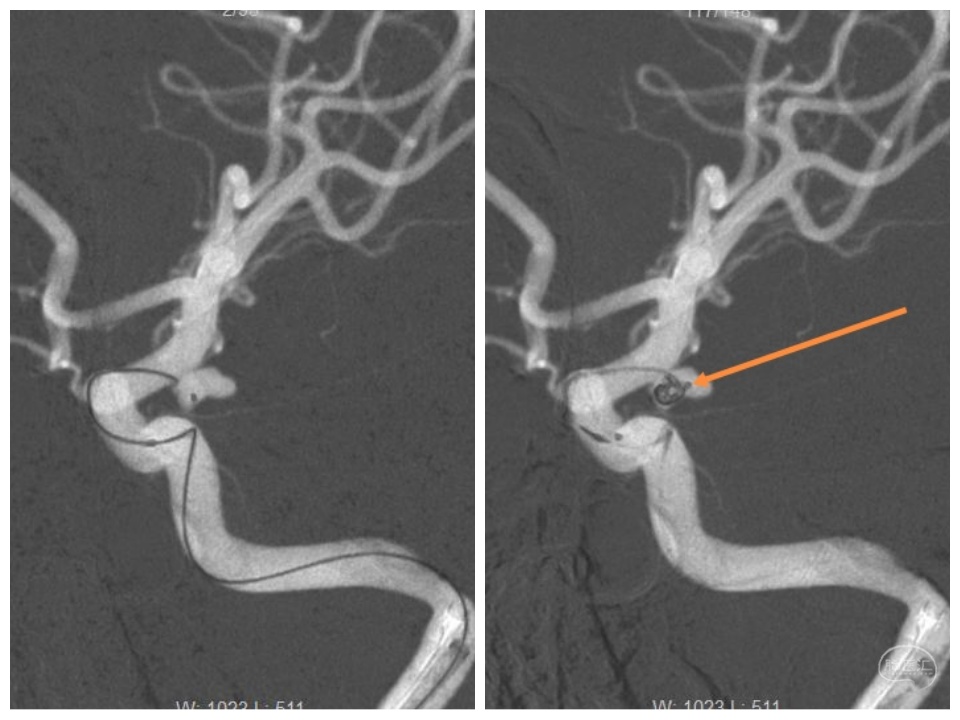

两根微导管到位(箭头示微导管2),先经过微导管1植入一枚,三维Target3-4弹簧圈,不解脱。

再经过微导管2植入一枚,三维Target2-6弹簧圈。

再经过微导管2,植入一枚二维target2-4弹簧圈。

解脱第一枚弹簧圈,经过微导管1,继续填塞,二维Target2-4、APB1.5-4-3D-ES、APB1.5-2- HX-ES、APB1-4-3D-ES各一枚。

撤出微导管1,可见该微导管占据的缝隙,此处仍空虚。

造影

继续经过微导管2植入:APB1-3-3D-ES、二维Target1-2各一枚。